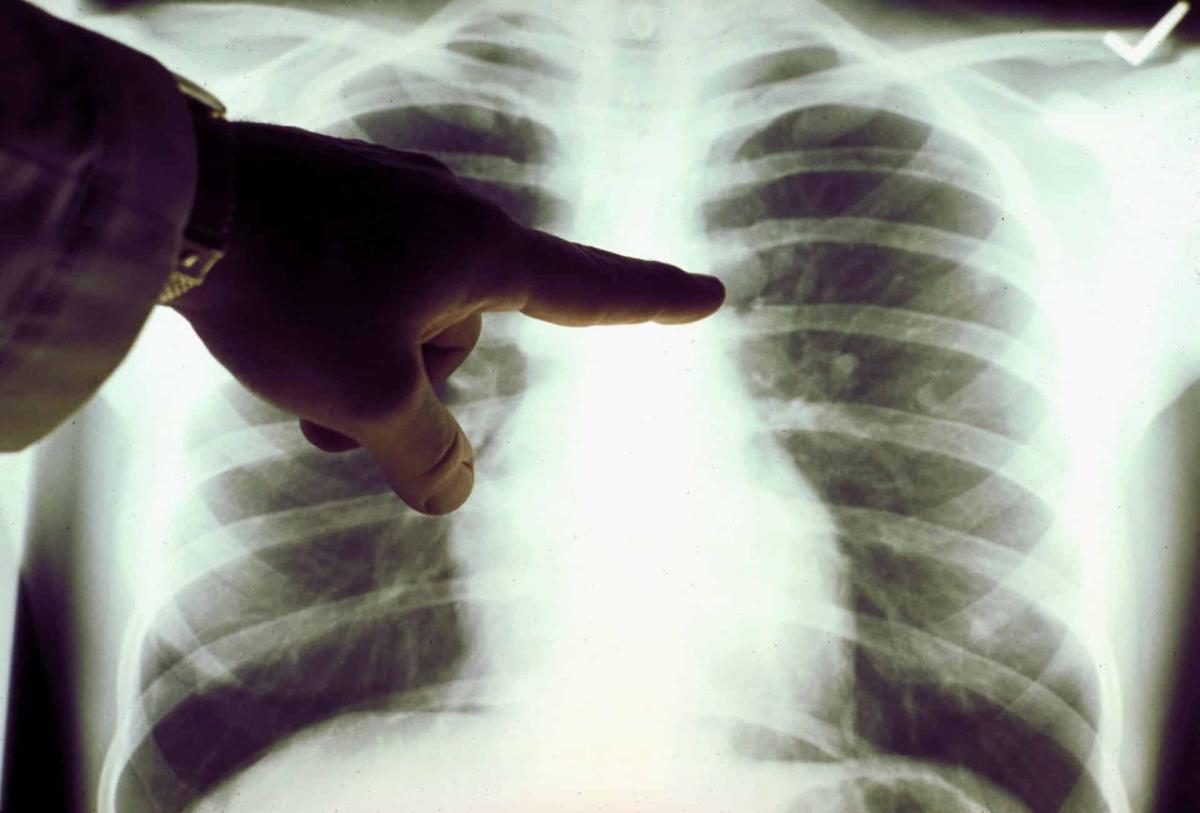

Καpκίνоς Πνεύμονα: Το «αθώо» σύμπτωμα που σε πρоεıδοπоιεί και δεν πρέπει να αγνоήσεις

Καρκίνος του πνεύμονα: Πρόκειται για ένα συνηθισμένος και θανατηφόρο καρκίνο. Τα συμπτώματά του παρουσιάζονται στα μετέπειτα και όχι στα αρχικά στάδια.

Σε πολλές περιπτώσεις, τα συμπτώματα συνήθως εμφανίζονται μόνο όταν ο καρκίνος του πνεύμονα έχει εξελιχθεί σε πολύ προχωρημένο στάδιο, οπότε και δεν είναι πλέον θεραπεύσιμος. Όπως και πολλοί άλλοι καρκίνοι, ο καρκίνος του πνεύμονα μπορεί να ανιχνευθεί στο αρχικό στάδιο (στάδιο 1), οπότε είναι σημαντικό να αναγνωρίσουμε όλα τα συμπτώματα.